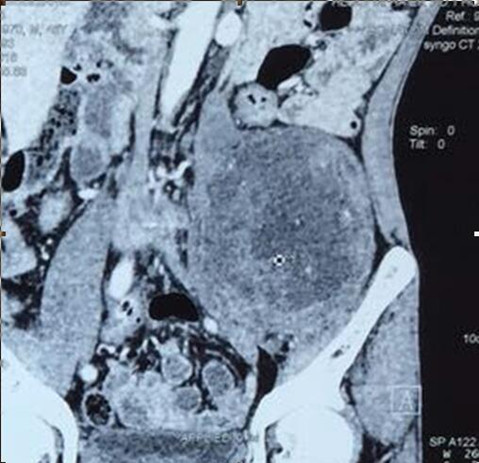

左侧盆腔椎体旁腹膜后巨大肿物切除

赵先生45岁,于2015年7月发现左侧腹部有一无痛性肿物,约鸡蛋大小,赵先生认为这肿物不痛不痒,就没重视。可随着时间推移,肿物逐渐增大,李先生出现左下肢疼痛、麻木的症状,包块增长至约拳头大小,疼痛明显加重,甚至无法入睡,严重影响李先生生活质量,仅半年时间,体重减轻10kg,在外院行增强CT检查示:“左侧腹膜后占位,考虑间叶源性肿瘤可能性大”。为求进一步诊治,李先生多方打听来我院骨外一科就诊。确诊后,白玉江主任决定为此其行肿物切除术。术中见腹外斜肌下方肿物,手术难度及风险极大,经过两个小时的手术,最终将15×10×10cm3巨大肿瘤完整切除。术后病理回报:粘液性脂肪肉瘤。术后一个月及两个月随访,患者左下肢疼痛无复发。

手术难度:由于患者有肿瘤病史,且此重物巨大在盆腔内,无活动度,手术难度极大,因肿物巨大与周围组织粘连,手术时间较长,并极有可能造成输尿管、腹膜、肠管、神经的损伤;该肿瘤恶性可能性大,若侵犯周围组织,需扩大切除;其中最危险的是肿物在盆腔与左髂骨粘连且无活动度,若将其完整切除极有可能损伤盆底静脉丛,造成大量失血,引起失血性休克导致患者死亡。

入院后腹部MRI